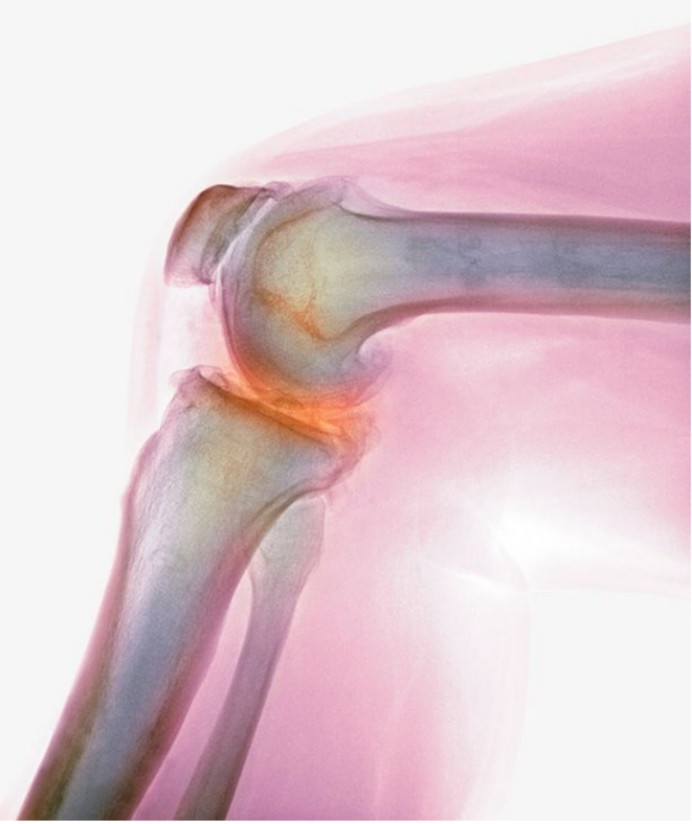

法贝骨是什么呢?

法贝骨原本是属于膝盖骨当中的一块籽骨,由于在人体

法贝骨,一般在哺乳动物的身上比较常见,尤其是灵长

在19世纪70年代的时候,科学家们首次发现了法贝骨的